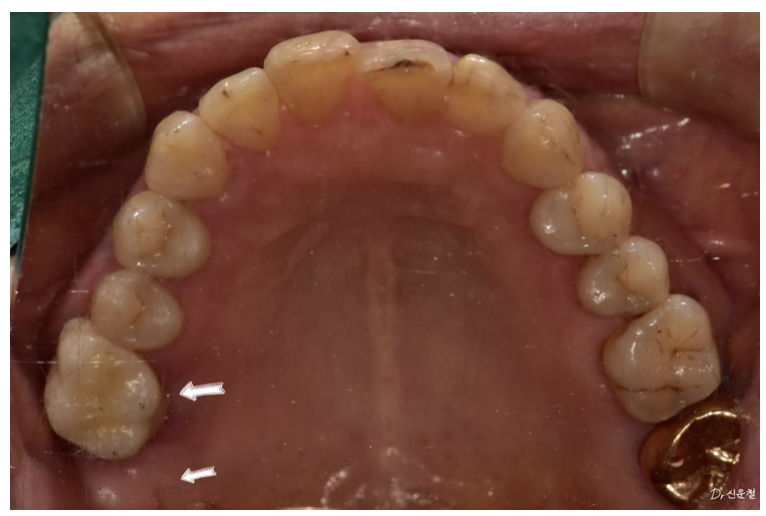

촬영일 : 250825

겉으로 보기에는

두 치아 모두 발치가 필요해 보였지만

자세히 검사해 보니 상황이 조금 달랐습니다.

한 치아는 염증이 넓게 퍼져

발치가 더 안전한 상태였고

다른 치아는

신경치료를 통해 충분히 사용할 수 있는 상태였습니다.

그래서 두 치아를 모두 발치하는 대신

한 치아는 발치

한 치아는 신경치료

이렇게 치료 방향을 나누었습니다.